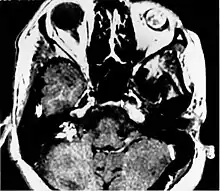

Post contrast T1 weighted MRI demonstrates intense enhancement of both the eye and the endolymphatic sac tumor in patient with VHL.

Imaging studies help to identify the tumor and the specific anatomic site of involvement. Magnetic resonance images show a hyperintensity (hypervascularity) of a heterogeneous mass by T1 weighted images. Computed tomography shows a multilocular, lytic destructive temporal bone mass, centered on the vestibular aqueduct (between internal auditory canal and sigmoid sinus).[1][6][7]